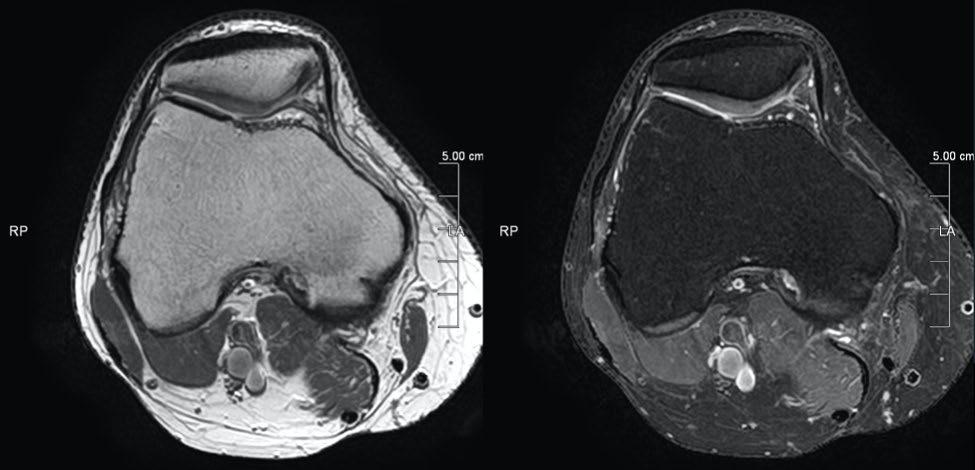

AiCE - High resolution imaging with short scan times

Ankle

16ch Flex SPEEDER, WFS (Water Fat Separation), AiCE, Res: 0.3 x 0.3 x 3 mm,

Scan time: 3:13 min.

Shoulder

16ch Flex SPEEDER, T1, AiCE + Compressed SPEEDER, Res: 0.26 x 0.26 x 4 mm (interp),

Scan time: 1:00 min.

Lumbar Spine T1

Atlas SPEEDER Spine, AiCE + Compressed SPEEDER, Res: 0.35 x 0.35 mm, Scan time: 0:59 min.

Lumbar Spine T2

Atlas SPEEDER Spine, AiCE + Compressed SPEEDER, Res: 0.3 x 0.3 mm, Scan time: 0:57 min.

T2. T1. PD – In Phase. PD – Water Only.